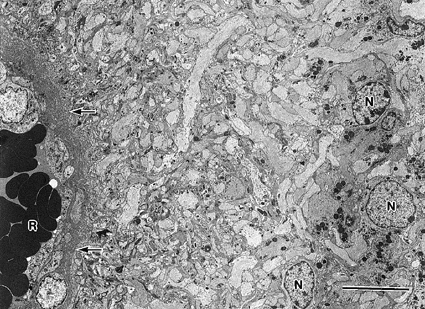

| 【電顕的観察】 | |||||||||

| 電顕では、本腫瘍が有するgliaとしての形態と上皮としての分化形態とをともに確認することができるので、きわめて有用な診断手段となっている。 所見的には、腫瘍細胞はgliaの基本性格として10nm径の中間系フィラメント(intermediate filament)を有する。また、上皮への分化形態としては、細胞間結合装置(tight junction)で接合し、微絨毛(microvilli)や線毛(cilia)を有する。 |